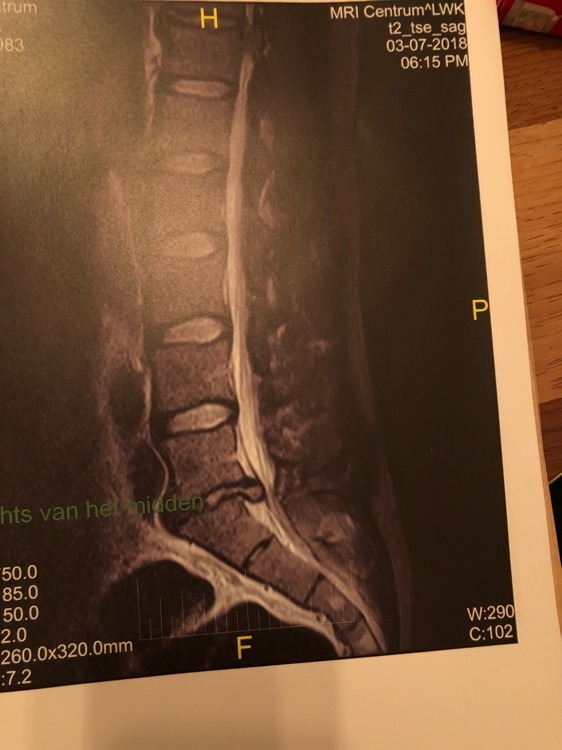

kan me voorstellen dat dat goed zeer doet zoals ie tegen de zenuwen aan duwt. Hopelijk kunnen ze je snel helpen.

en natuurlijk maanden, jarenlange overbelasting in onze oh zo "dankbare" sport, in combinatie met genetisch benadeeld voor wat betreft de rug vanuit moeders zijde.

Sinds wanneer kan iedereen hier MRI's analyseren